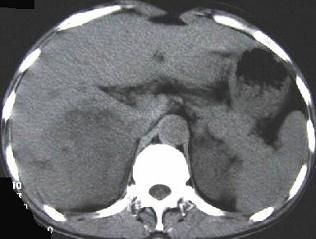

问题 男,45岁,右上腹痛,有发热,白细胞计数升高,CT检查如图,最可能诊断是 ( )

选项 A、肝黄色肉芽肿 B、肝转移癌 C、肝包虫病 D、肝脓肿 E、原发性肝癌

答案 D